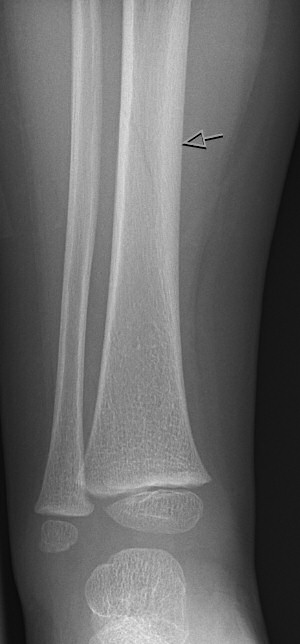

Toddler's fracture: nästan osynlig spricka (fissur) i tibiadiafys i ålder ca 9 månader - 3 år.

Toddler's fracture